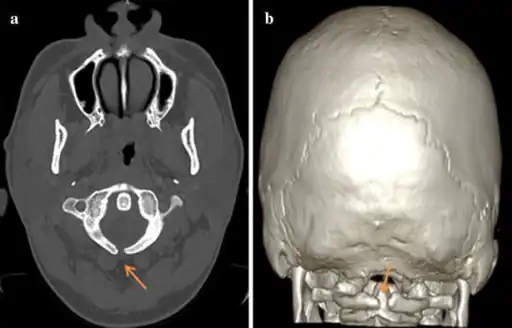

a,b) Atlas spina-bifida oculta

X-ray computed tomography scan of unfused arch at C1